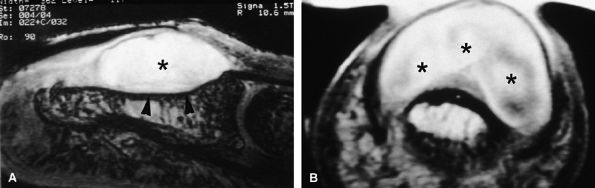

FIGURE 11.84 ● Macrodystrophia lipomatosa of the thumb. Axial (A and B) and sagittal (C) T1-weighted images depict thickening of the subcutaneous fatty tissue of the palmar and medial aspect of the thumb (asterisk). A fibrolipoma of the two first interdigital nerves demonstrates a cable-like pattern (arrows).

one third of cases are associated with macrodactyly (macrodystrophia lipomatosa) with bony and soft tissue overgrowth.195